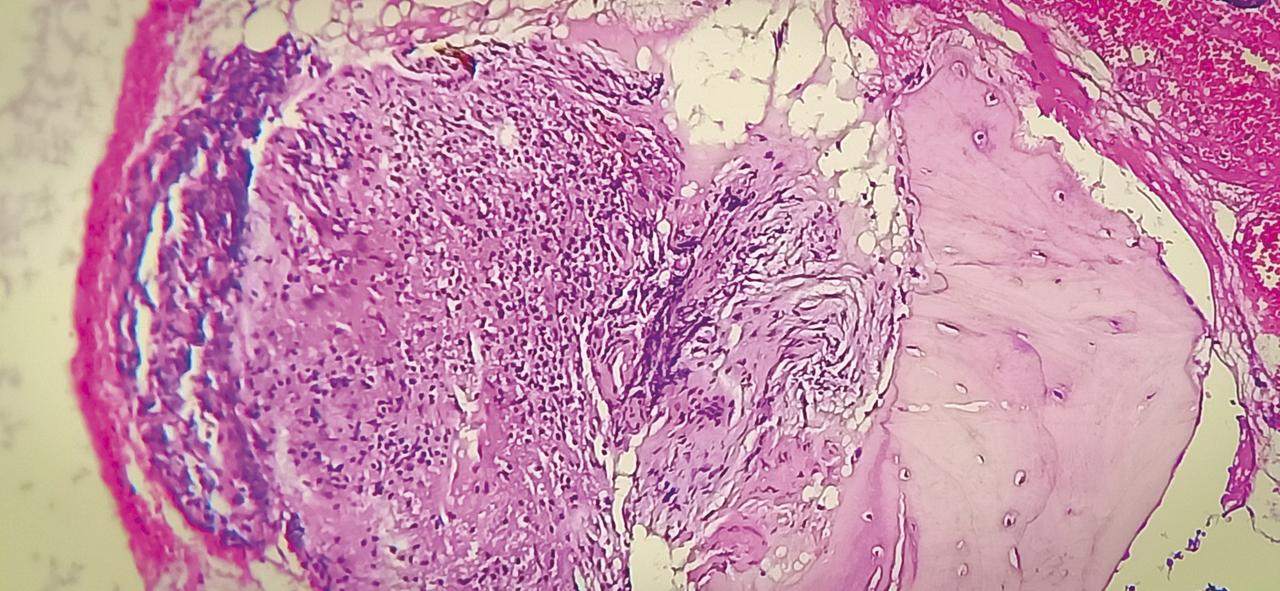

Cet homme de 53 ans consultait pour une douleur de la charnière dorsolombaire à irradiation antérieure, mal calmée par les antalgiques, avec un amaigrissement sans fièvre. L’examen clinique trouvait une raideur rachidienne et le bilan biologique montrait un syndrome inflammatoire. La tomodensitométrie (TDM) abdominale révélait une fibrose rétropéritonéale avec lyse de L1 (fig. 1 ). L’imagerie par résonance magnétique (IRM) montrait un aspect de fibrose rétropéritonéale secondaire, en hyposignal T1 et T2, se rehaussant après injection du gadolinium avec lyse de L1 (fig. 2 ). La tomographie par émission de positons au 18-fluorodésoxyglucose (TEP18-FDG) montrait un hypermétabolisme intense de L1 dont la biopsie scannoguidée révélait un granulome épithélio-giganto-cellulaire cadrant avec une tuberculose (fig. 3 ). Le patient était efficacement traité par les antibacillaires pendant 9 mois.

Figure 1. TDM, coupe axiale, fibrose rétropéritonéale refoulant l’aorte en avant avec lyse de L1.